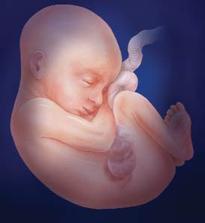

Lékaři počítají týdny těhotenství od prvního dne poslední menstruace před otěhotněním. V prvních dvou týdnech tehotenství tedy žena těhotná není, protože k oplodnění vajíčka dochází až zhruba 14 až 21 dní od začátku menstruace.

1.-2. týden těhotenství

Vajíčko ve vejcovodu čeká zhruba 12 až 24 hodin na příchod spermií. V ejakulátu je v průměru 250 milionů spermií, z toho pouze zhruba 400 se dostane až k vajíčku ve vejcovodu, přičemž cesta z pochvy do vejcovodu trvá spermiím až 10 hodin. Obvykle pouze jedna spermie uspěje a pronikne po zhruba 20 minutách snahy do vajíčka. Tím dojde ke vzniku oplodněného vajíčka, tzv. zygoty. V příštích 10 až 30 hodinách dochází ke splynutí genetických informací vajíčka a spermie. Pohlaví dítěte je určeno již v této chvíli – pokud spermie nese chromozom Y, narodí se chlapec, pokud chromozom X, narodí se dívka.